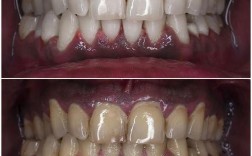

咬合关系是正畸评估的重点,直接影响咀嚼功能与面部美观,测量内容包括覆牙合、覆盖、中线偏斜及牙合曲线。

覆牙合:指下颌前牙切缘覆盖上颌前牙牙冠的垂直距离,分为三度:Ⅰ度(覆盖1/3牙冠高度内)、Ⅱ度(覆盖1/2-2/3)、Ⅲ度(覆盖2/3以上或下颌前牙咬至上颌硬腭),测量时需患者正中咬合,用探针或游标卡尺记录覆盖深度,深覆牙合需结合 Spee 曲线深度判断垂直向问题。

覆盖:指上颌前牙切缘与下颌前牙切缘的水平距离,正常值约为2-4mm,覆盖过大(深覆盖)可能与上颌前突、下颌后缩或牙列间隙有关;覆盖为负值(反覆盖)即反牙合,需区分骨性与牙性反牙合。

中线偏斜:测量上颌中切牙中缝与下颌中缝的水平距离,反映上下颌骨与牙列的对称性,中线偏斜可能由单侧后牙早接触、下颌偏斜或牙量骨量不调导致,需结合颞下颌关节检查明确病因。